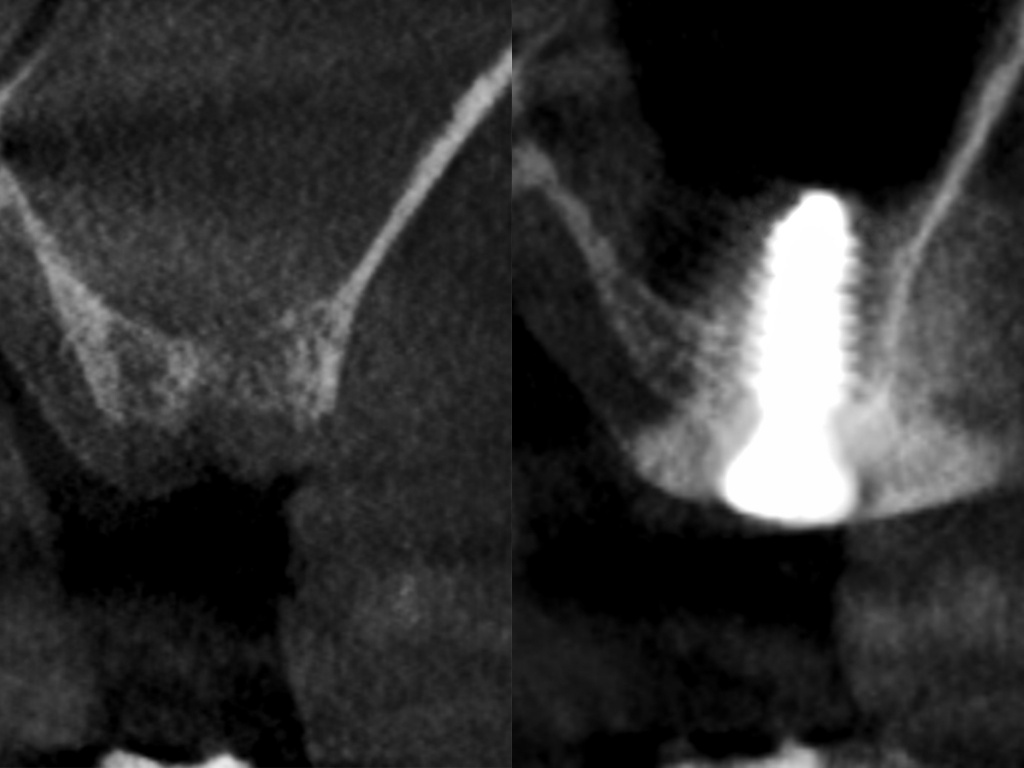

Имплантация AnyRidge с двусторонним закрытым синус-лифтингом.

Осложнения: правосторонний гайморит.

Кейс MINEC: Dr Lu Du